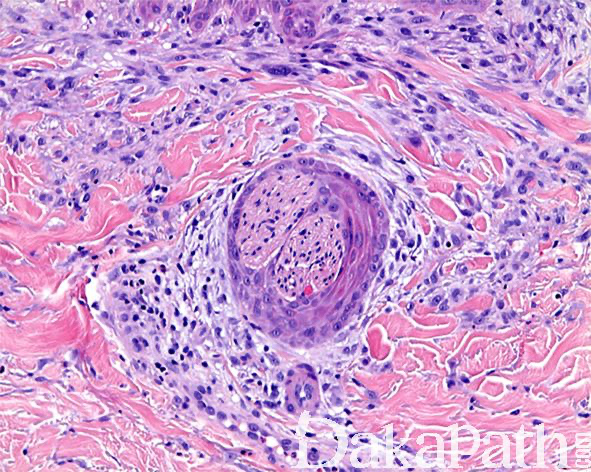

镜下见病变位于真皮浅层,由多个增生的神经束组成,神经束周围可见由鳞状上皮所组成的鞘样结构围绕,神经束内可见轴突、施万细胞和神经束膜细胞;

上皮鞘常与表面上皮相延续,细胞形态温和,可见散在的角化不良的细胞,无核异型性和核分裂象,可能来自于毛囊特别是漏斗部上皮;

表面鳞状上皮常见棘皮瘤样增生;

上皮鞘周围间质内可见疏松的纤维化和多少不等的淋巴细胞浸润。